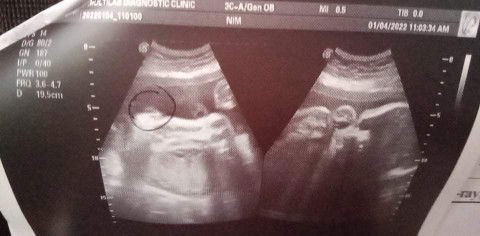

mga momsh tanong ko lang po mejo nag hesitate po kasi ako sa result ng ultrasound ko about sa gender hindi nilagay ng doctor anu gender nya pero pinakita nya naman po sakin, kaso hindi satisfied sa result ang mister ko kasi hindi daw inilagay sa result mismo ung gender mahirap na daw e baka nanghula lang ang doktor.. pero sa utz ko po meron sya binilugan doon.. anu po kaya talaga meaning nito? baka may mga ob po tayong member dito, salamat po. #advicepls #pregnancy